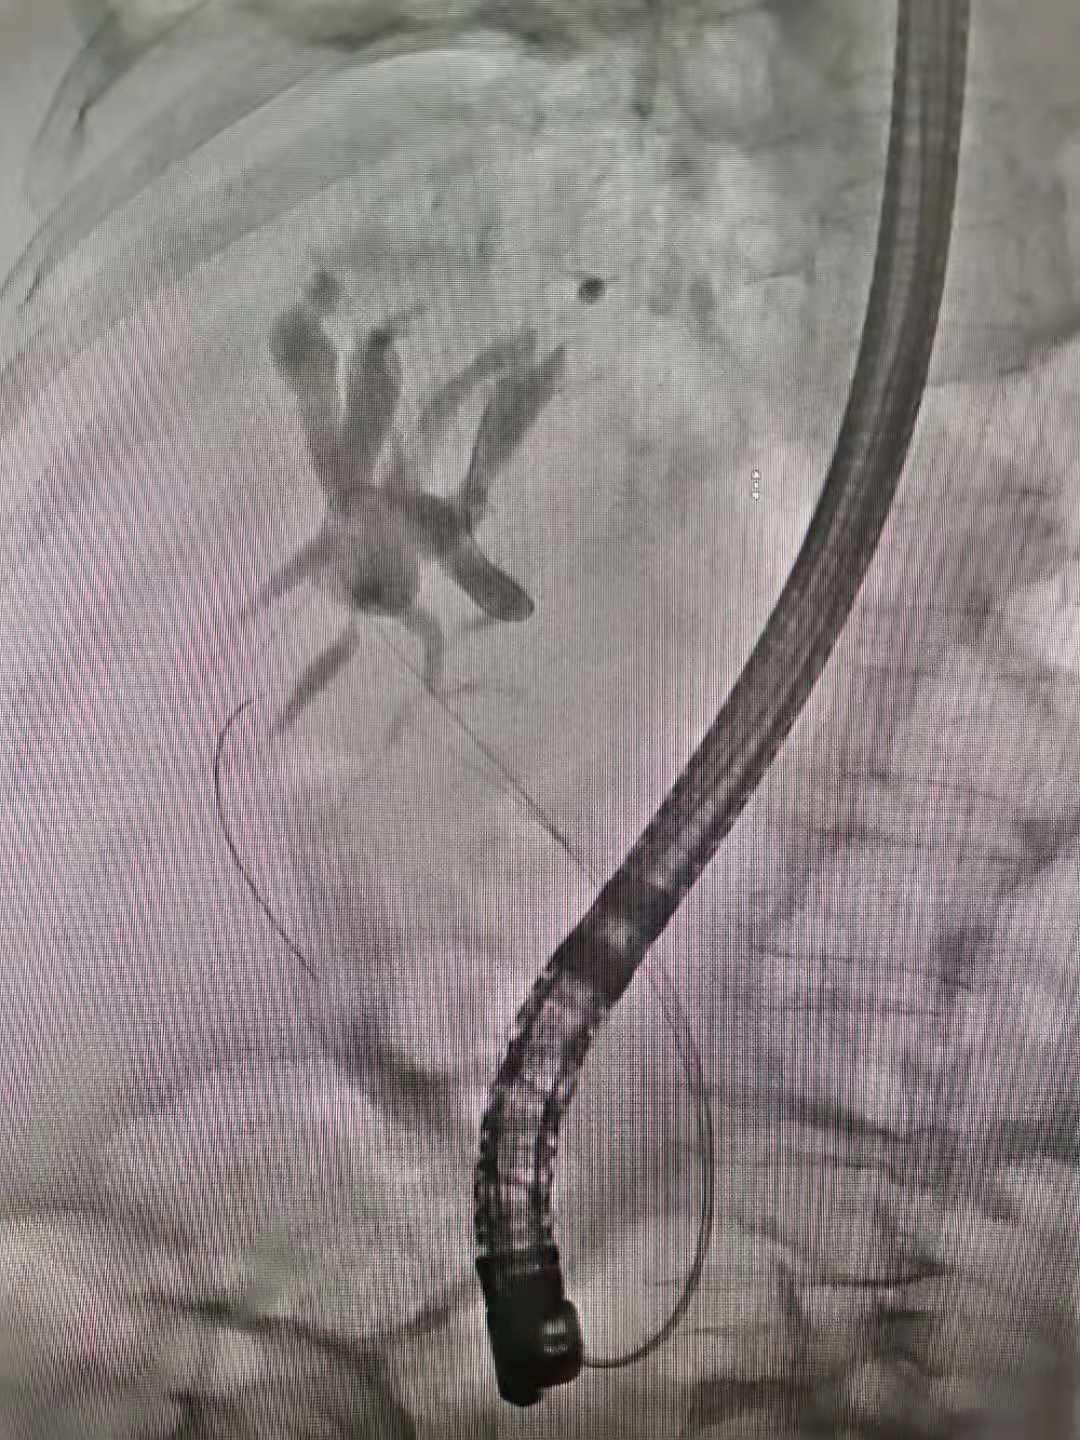

在科主任温志立教授的指导下,由章诺贝教授带领的红角洲院区胆胰团队对李奶奶的病情进行了充分的评估及研讨,最终决定行经内镜逆行胰胆管造影(ERCP)取石治疗胆总管结石的微创治疗。然而,ERCP虽简便、安全,但操作起来却并不容易,是操作难度及技术要求最高的内镜手术之一。

胆胰管开口在十二指肠降部,ERCP操作需将十二指肠镜从口腔插入患者体内,经食管、胃部至十二指肠降部、经十二指肠乳头注入造影剂,由于镜身盘绕及视线局限,很难前进,可谓每一毫米都需要调整定位,非常考验操作者的技术。经过反复探查找到李奶奶的嵌顿于胆总管内的(异物)塑料支架,章诺贝教授迅速插入取石网篮将其安全取出,同时见数枚大小不等的结石随之掉入十二指肠腔内,而结石最大者足有10毫米。术中并留置5根塑料支架于肝总管,为避免支架滑脱置入一枚和谐夹于乳头表面进行塑形,最后置入一根鼻胆道引流管于左肝管,胆汁引流通畅,全操作过程一气呵成,耗时五十分钟!